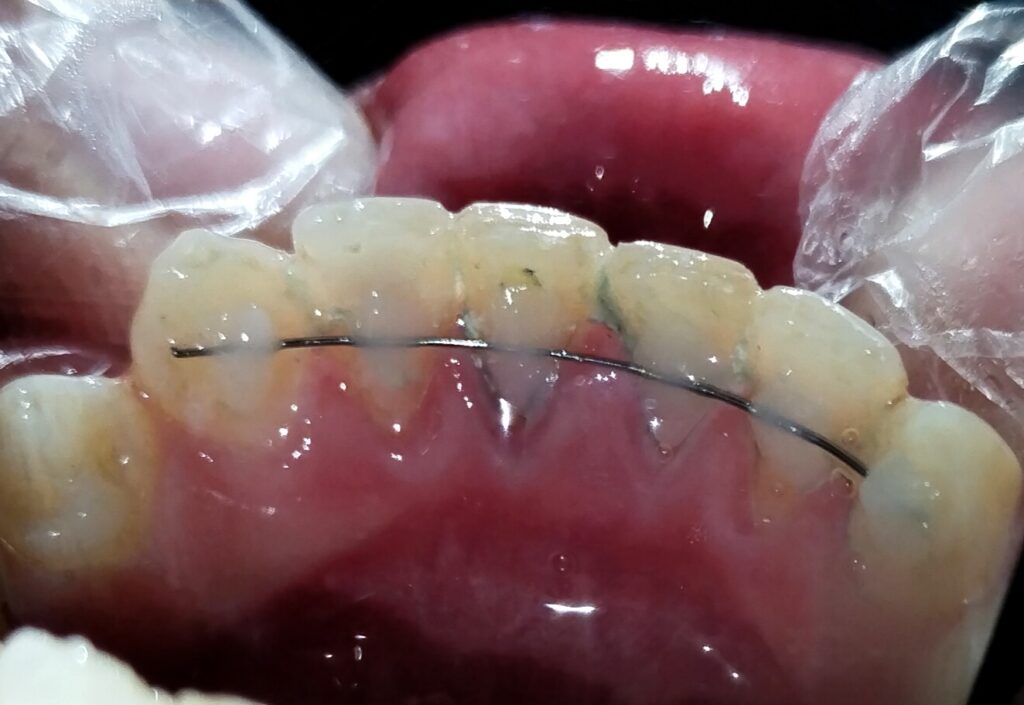

Our approach focused on preserving Muzakkir’s natural dentition while promoting optimal healing. We opted for root canal treatment in the central incisors to address pulp involvement and prevent further complications. Additionally, we implemented a splinting technique, stabilizing the affected teeth from canine to canine to facilitate alignment and reduce mobility.